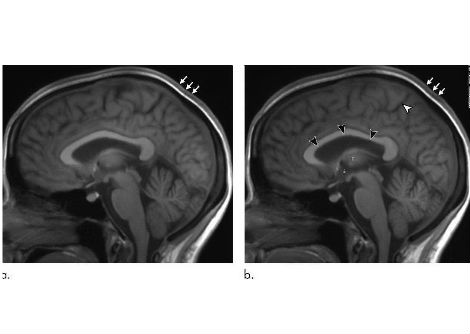

وفقًا لتقرير الفريق المنشور في مجلة Frontiers in Aging Neuroscience ، كان الباحثون يراقبون أولاً موجات الدماغ لمريض الصرع البالغ من العمر 87 عامًا بحثًا عن نوبات باستخدام معدات تخطيط كهربية الدماغ (EEG).

ومع ذلك ، أصيب المريض بنوبة قلبية وتوفي وهو لا يزال مرتبطًا بمخطط كهربية الدماغ . أتاح هذا للباحثين فرصة لا تتكرر في العمر لالتقاط 15 دقيقة من نشاط الدماغ لشخص يحتضر.